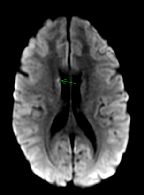

A Case of Synthetic Cannabinoid Induced Ischemic Stroke in A 20 Year Old Female

Darshan Manix, Haidy Youssef, Joseph Ling, Arnon Desai, Rajesh Gulati*